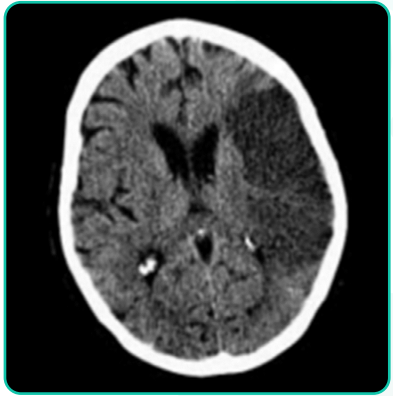

Mulher de 75 anos de idade é hipertensa em uso de enalapril 20 mg, 2 vezes ao dia, e diabética em uso de metformina. Apresentou, há 5 horas, hemiparesia direita associada com desvio de rima para a esquerda e dificuldade de falar. No exame clínico: bom estado geral, consciente, desorientada temporal e espacialmente, afebril, acianótica e anictérica. Pressão arterial = 180 x 100 mmHg; pulso = 110 bpm, irregular. Ausculta cardíaca com bulhas arrítmicas e normofonéticas em dois tempos, sem sopros. Apresenta hemiparesia completa e desproporcionada à direita, disartria, afasia motora e hemi-hipoestesia completa. O restante do exame clínico está sem alterações. Foi realizado ECG de 12 derivações que confirma a impressão de fibrilação atrial e TC de crânio (a seguir). A angioTC revela oclusão da artéria cerebral média esquerda. Sobre o quadro em questão, qual das alternativas está correta?